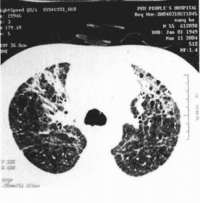

胸部X线检查早期可无异常,一般1周内逐渐出现肺纹理粗乱的间质性改变、斑片状或片状渗出影,典型的改变为磨玻璃影肺实变影。可在2-3天内波及一侧肺野或两肺,约半数波及双肺。病灶多在中下叶并呈外周分布。少数出现气胸纵隔气肿。CT还可见小叶内间隔和小叶间隔增厚(碎石路样改变)、细支气管扩张和少量胸腔积液。病变后期部分患者肺部有纤维化改变。

SARS

SARS2